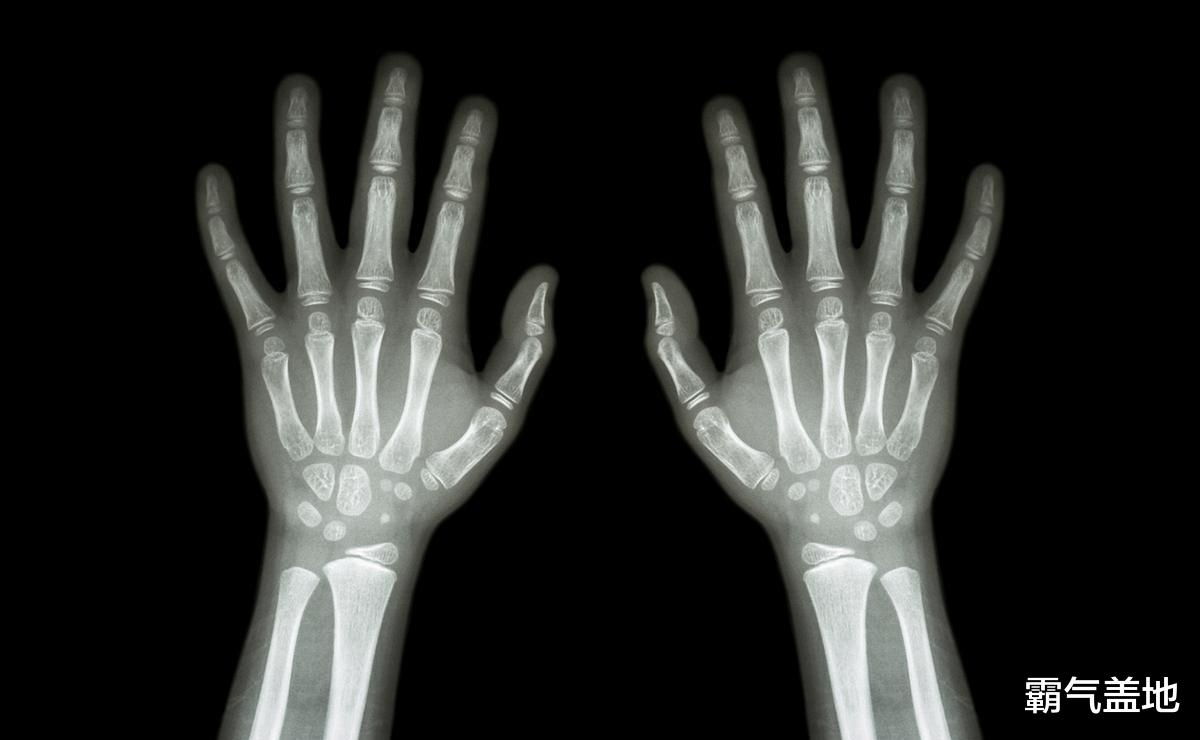

骨骺线到底是个啥?简单来说,它位于我们长骨的两端,决定了孩子还能不能继续往上“窜一窜”。 想想建造房子,骨骺线就像是建筑工地上辛勤的工人,在生长激素的指挥下,不停地增殖、钙化,一点一点地把骨头拉长。

最简单的方法,就是摸摸孩子的手指。 如果你发现孩子的手指骨骼摸起来完全“硬邦邦”的,关节附近也摸不到软骨的那种感觉,那可就要注意了,这很可能暗示着骨骺线即将闭合。或者,你可以观察孩子手指的长度,如果好几年都没有明显变化,也要警惕起来。

还有一些其他的“小前兆”也值得关注。 比如说,孩子的生长速度突然慢了下来,以前一年能长个5-10厘米,现在一年只能长个1-2厘米。 再比如,孩子的第二性征发育加速,女孩乳房开始发育,月经初潮;男孩喉结变大,声音开始低沉。 另外,孩子的脚丫子也可能不再“长大”,鞋码趋于稳定。 如果条件允许,可以带孩子去医院做个骨龄检测,看看骨龄是不是比实际年龄超前了。